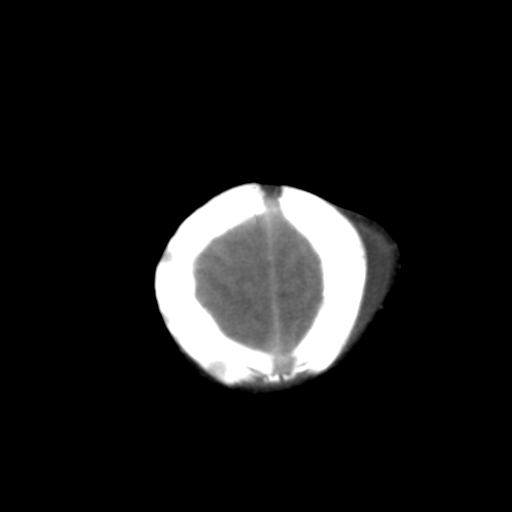

男,3天,患儿为剖腹产,生后嗜睡、拒乳。

脑室系统及脑沟裂闭塞,弥漫性脑密度减低,支持考虑hie,建议复查。右侧颞顶枕部及左侧颞顶部头皮血肿,另不除外胼胝体发育不良,复查